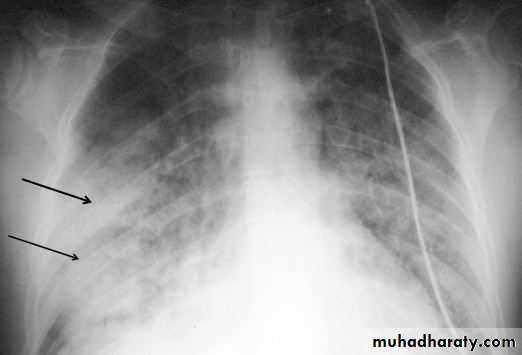

Lung contusion